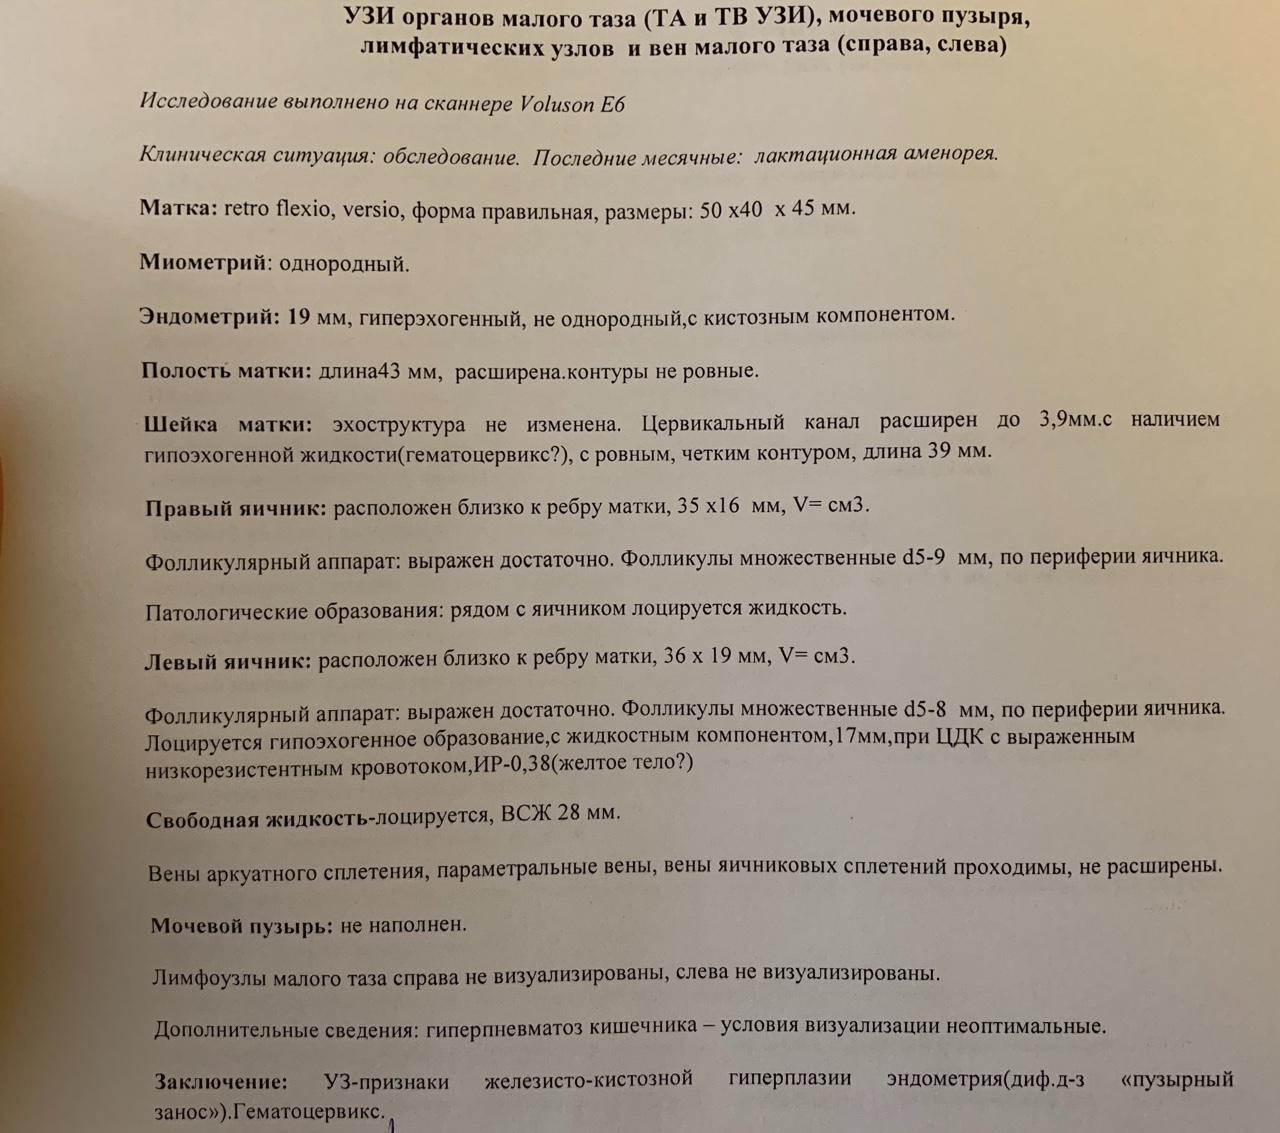

Медицина и диагностика: Инвазивный пузырный занос на УЗИ

Раздел: Альбом идей